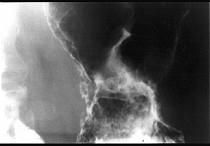

男,65岁,中上腹痛半年,X线检查如图,最可能的诊断是 ( )A.胃息肉B.胃溃疡C.胃浸润癌D.胃间质瘤E.糜烂性胃炎

问题 男,65岁,中上腹痛半年,X线检查如图,最可能的诊断是 ( )

选项 A.胃息肉 B.胃溃疡 C.胃浸润癌 D.胃间质瘤 E.糜烂性胃炎

答案 C